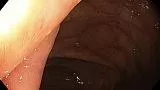

Пациент К.,60 лет, направлен на плановую колоноскопию с жалобами на длительную диарею и боли в правой подвздошной области, в анализах повышенный фекальный кальпротектин. На колоноскопии обнаружена одиночная язва у входа в илеоцекальный клапан , неправильной формы, с глубоким дном, на дне белый детрит, вокруг выраженные воспалительные явления, вокруг поверхностный рисунок при осмотре изменен, нерегулярный, взята биопсия. Илеоцекальный клапан не проходим для колоноскопа. На гистологии- язвенный дефект с дисплазией высокой степени, Болезнь Крона.

Колоноскоп- Olympus HQ-190. Осмотр  в режимах NBI  и  Near Focus.